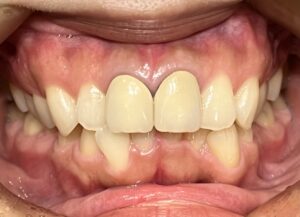

メンテナンスでいつもお越しいただいている長年の患者様が、

「前歯をもう少し綺麗になおしたい」「歯茎との境が黒くなっているのが気になる」とのことで、

仕事や生活の都合上、タイミングがあったので今回審美治療をスタートすることにしました!

元々、上の前歯に入っている補綴物の状態がこちらです。

歯と歯茎の境が黒くなっているのがわかります。

まずは元々入っている補綴物を外し、仮の歯を入れていきます。

仮歯を入れた状態がこちらです。

歯科治療において、仮歯の役割はとても重要になります。

嚙み合わせの状態や、審美的な見た目など、

仮歯の段階で何かしらのエラーに気づくことができれば事前に修正することができます。

歯肉が安定してきたら、最終の補綴物を入れる前に

天然の歯にホワイトニングをかけていきました。

白くなった歯に合わせて最終の補綴物を入れていきます。

そして前歯にフルジルコニアセラミッククラウンを入れた状態がこちらです。

Before After

歯と歯茎の境もなくしっかりとフィットし、綺麗な仕上がりになりました。

笑顔もとても素敵ですね♪